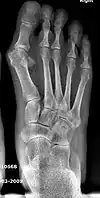

Primus varus deformity is the leaning of the first metatarsal bone away from the second metatarsal and towards the opposite foot (Fig. 1). As it leans over, its head sticks out to form the bunion bump and it also widens the forefoot to cause shoes feeling too tight. Thus when bunion pain becomes unmanageable, surgical correction is to narrow the forefoot by repositioning of the first metatarsal head back to its normal position. This can be done by osteotomy (bone-breaking), soft tissue (non-osteotomy) or fusion techniques.

- For recurrence correction after osteotomy procedure (Fig. 8)

Late deformity recurrence can happen after osteotomy (bone-breaking) procedures because osteotomy surgeries do not specifically stabilize first metatarsal bone.